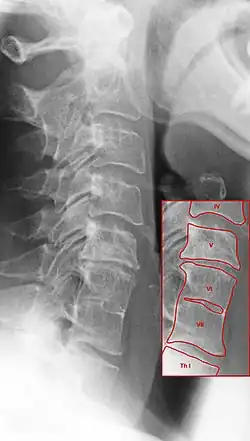

Röntgenbild der Halswirbelsäule mit Osteochondrose (V/VI) und Klippel-Feil-Syndrom (VI/VII)

Auch die verschleißbedingte Osteochondrose der Wirbelsäule bedingt eine Verschmälerung der Zwischenwirbelräume. Die Abbildung unten zeigt die Unterschiede: Die Osteochondrose zwischen Halswirbelkörper V und VI weist den betroffenen Wirbel überragende Exophyten auf. Zwischen den Wirbeln VI und VII dagegen sind solche Auswulstungen nicht zu sehen. Die dort sichtbare Verbindung der Wirbelkörper ist anlagebedingt und hat nichts mit Verschleiß zu tun. Tendenziell ist die Wirbelsäule dort sogar schmaler (deutlich zu sehen in der Aufnahme der Halswirbelsäule im Bild oben).